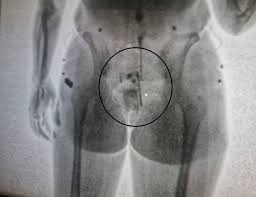

Os agentes penitenciários receberam informações de que a jovem tentaria entrar com entorpecentes na unidade prisional e, assim que ela chegou, a encaminharam para a Unidade de Pronto Atendimento (UPA) para exames médicos, que identificaram o entorpecente no corpo da mulher.